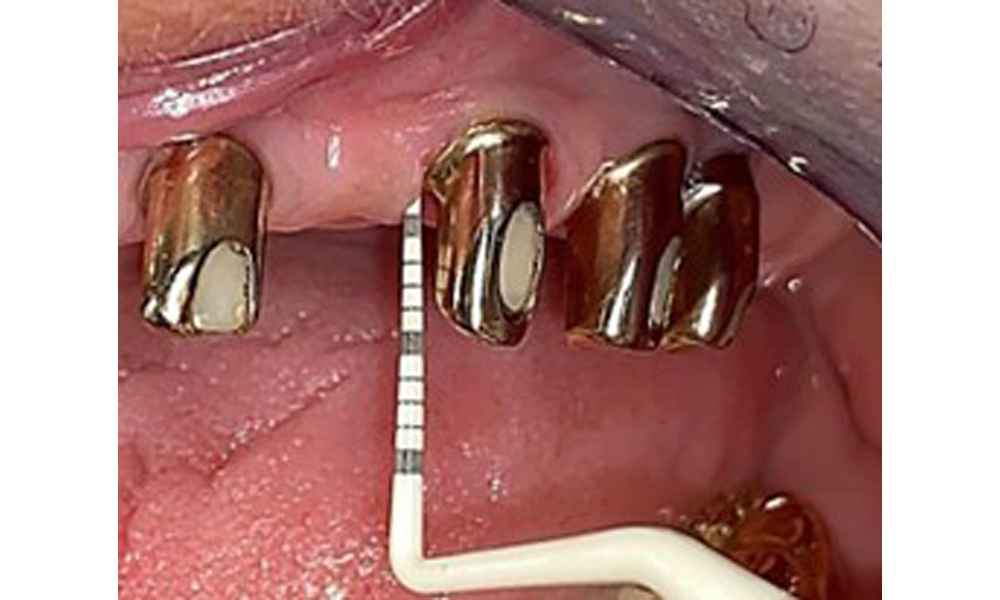

Die Patientin wurde vor über 25 Jahren mit einer kombinierten herausnehmbare Implantat-Teleskopprothese im Oberkiefer versorgt (Abb. 1, Abb. 2, Abb. 3) und ist sehr glücklich über ihren Zahnersatz. Im Unterkiefer hat die Patientin einen suffizienten festsitzenden Zahnersatz. (Abb. 4)

Der dentale Befund stellt sich wie folgt dar: Kombinierte herausnehmbare Implantat- und zahngetragene Teleskoparbeit auf Implantaten 15, 13, 21, 23, 24, 25 und Zahn 11 (Abb. 1, Abb. 2, Abb. 3). Im Unterkiefer ist die Patientin mit einem festsitzenden Zahnersatz versorgt. 37–34 sowie 45–47 haben suffiziente Brücken (Abb. 4). Kronenränder sind intakt, aktive kariöse Läsionen sind nicht vorhanden. An Zahn 43 zeigt sich eine Compositefüllung mit Randspalt. Im Unterkiefer liegen Rezessionen mit freiliegender Wurzeloberfläche zwischen 1 – 3 mm vor. Dies trifft auch für 11 zu.

Die Mundschleimhaut ist auf mögliche Pilzinfektionen und Druckstellen zu untersuchen. Der Zahnersatz muss optisch auf Sauberkeit geprüft werden. Im vorliegenden Fall zeigen sich interdental Verfärbungen, welche auf den Teekonsum zurückzuführen sind (Abb. 7). Der Zahnersatz sollte in der Praxis professionell gereinigt werden in entsprechenden Desinfektions- und Reinigungsbädern.